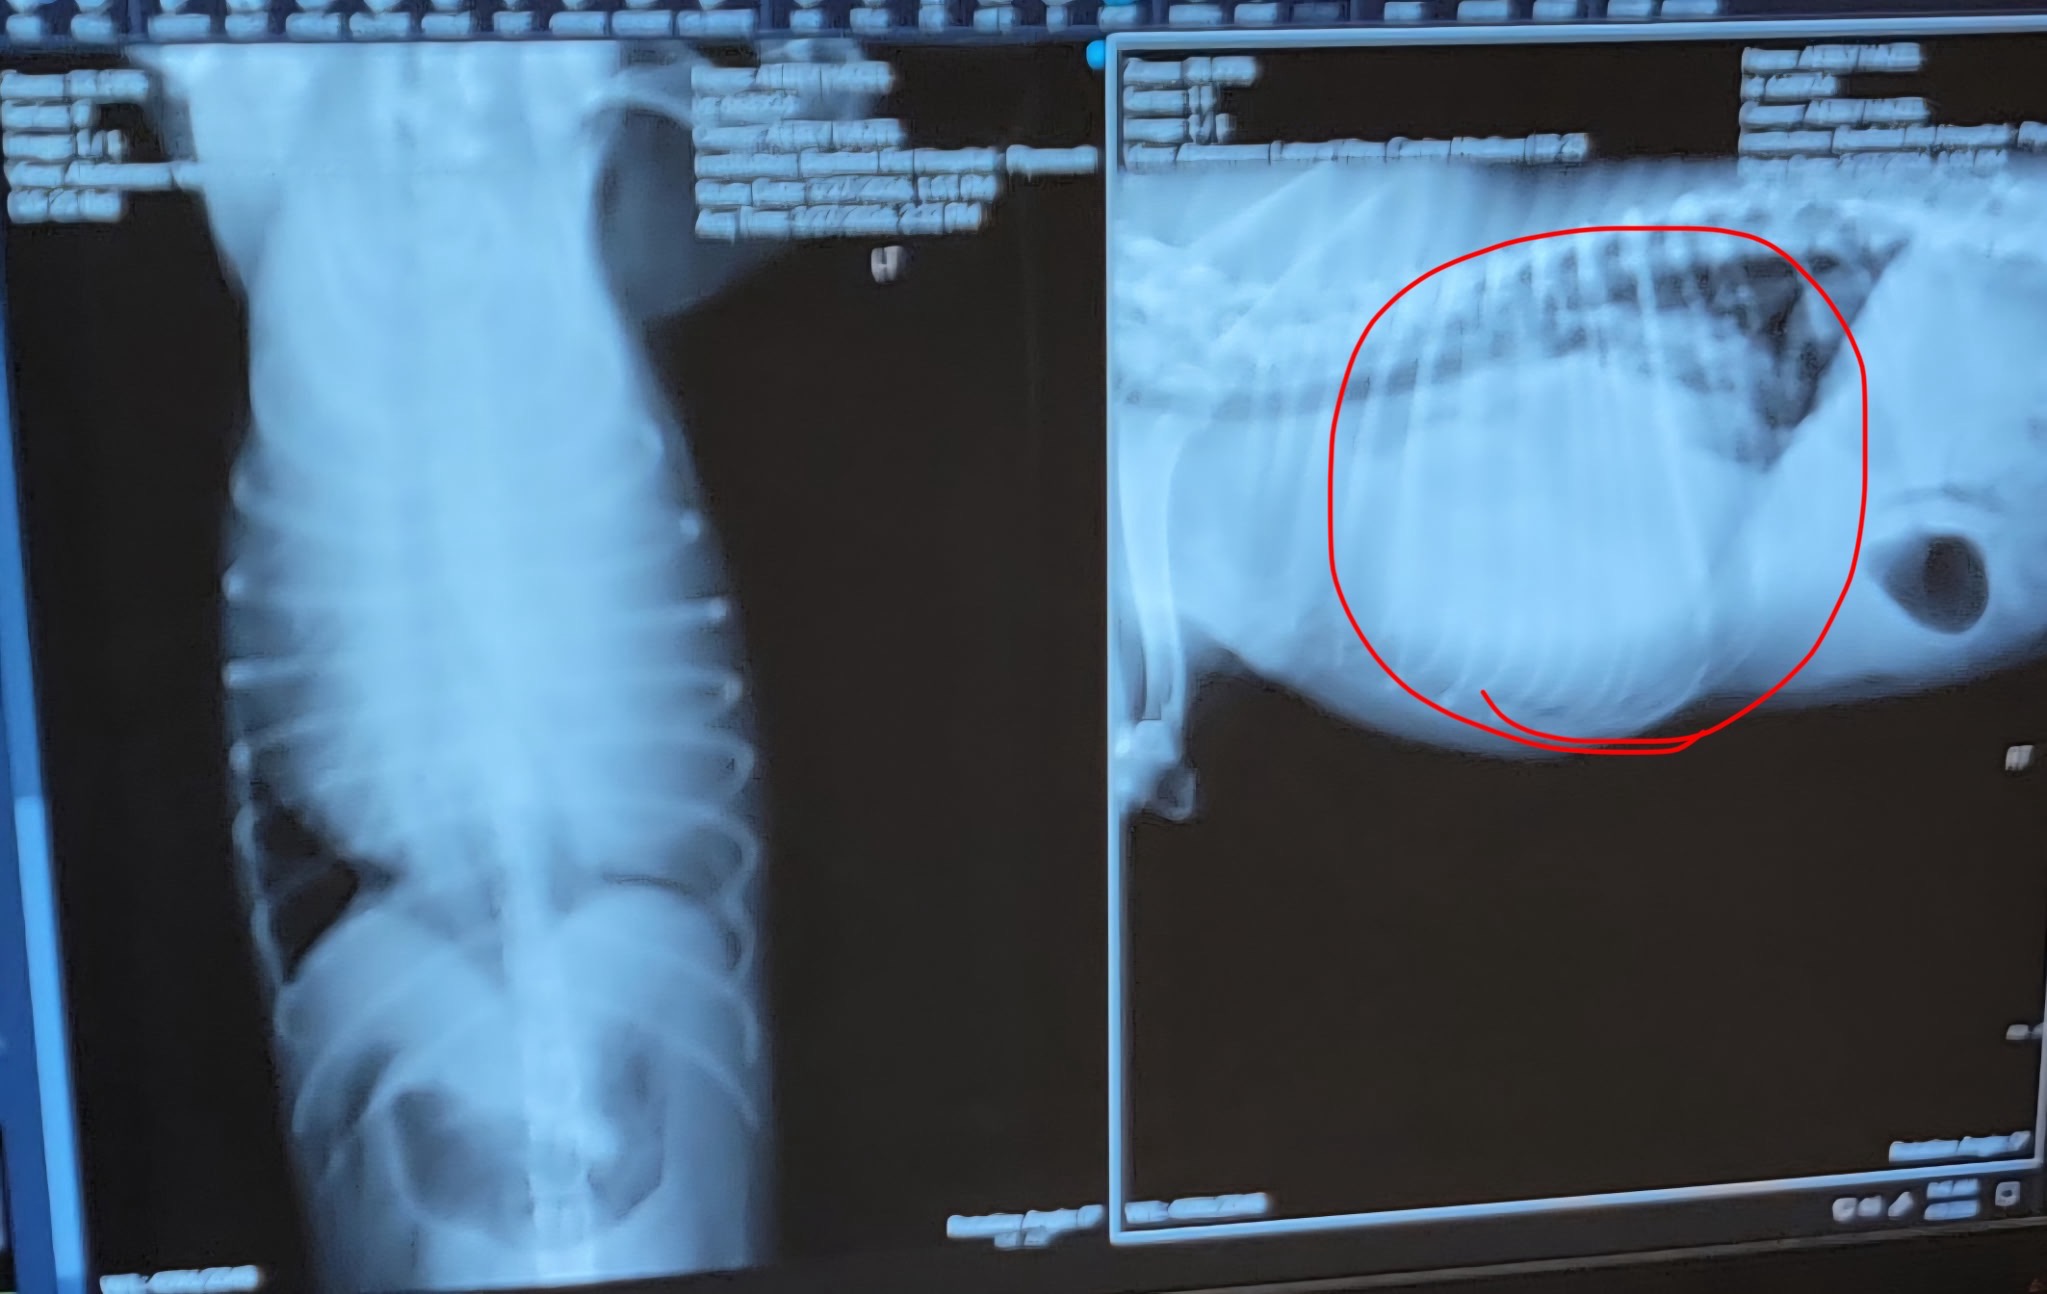

I’m asking for help for two of my closest friends, Allison and Jeremy, who are facing devastating news. Their dog, Hazel, has a tumor that is now affecting her breathing. After doing all the testing and everything they could, they’re currently at the vet being told it will cost $15,000 for the surgery to remove it.